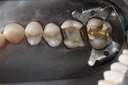

Wayne Chin #14 pre-op